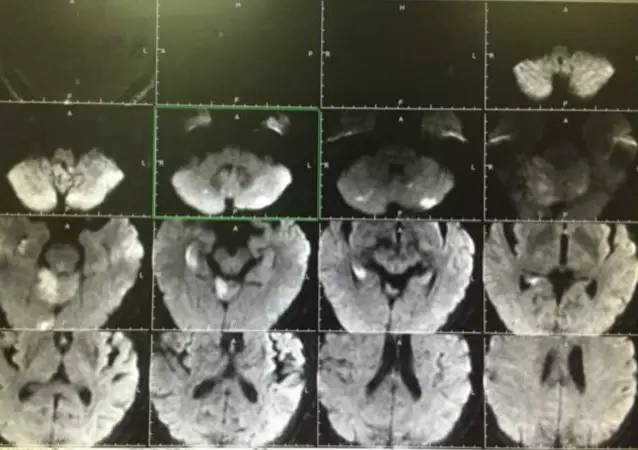

患者发病后三个半小时再通,现在恢复相当好,神志清楚、对答切题,四肢肌力正常!

▼术后复查头颅MRI显示小脑蚓部及小脑半球有散在的梗死灶,脑干未见梗死。头颅MRA显示后循环血管通畅。

▼有这样的结果那么病人恢复也一定是很满意的,术后3天患者完全恢复正常无任何神经缺失症状。